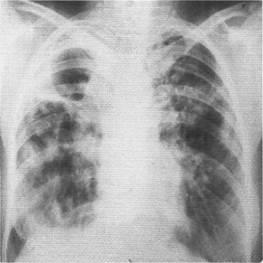

cavitate cu pereți subțiri umplut cu aer, dând cu umbra acoperite în interior și fiind descoperirea radiografică, caracteristic necomplicate pentru chist pulmonar închis inel. In prezenta simptomelor clinice caracteristice distrugerii pulmonare stafilococice astfel umbră indică formarea de degradare a cavității umplută cu aer, fundul care poate fi o cantitate mică de lichid (Fig. 1).

Fig. 1. X-ray a pacientului Ya 28 ani, într-o proiecție directă. În câmpul pulmonar mijlociu, se determină două cavități cu pereți subțiri, care măsoară 2x1,5 cm și 4x3,5 cm, umplută cu aer. O cantitate mică de lichid este detectată în partea inferioară a cavității mai mari. Distrugerea stafilococică a plămânilor